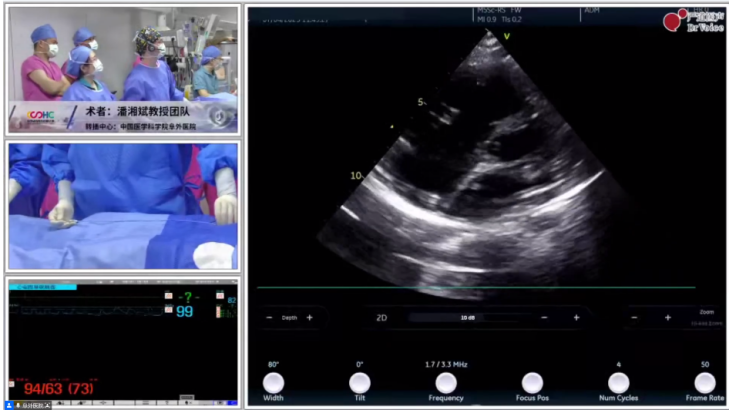

中国医学科学院阜外医院结构性心脏病团队在本次活动中演示数台单纯TTE引导下的可降解封堵器植入术,涵盖PFO、ASD、PDA等术式,全程零射线操作,术后无金属残留。团队通过实时超声精准定位,确保封堵器释放的精准性与生物相容性,为复杂先心病患者提供了微创、绿色的治疗方案。

术后的讨论环节中,与会专家们总结道,从PFO、ASD到PDA,每场手术都在诠释“介入无射线、植入无残留”的绿色理念,为推动国内结构性心脏病治疗向规范化、精准化、个性化发展提供了有力支撑。在单纯TTE引导下可降解PFO封堵器植入术,团队通过经胸超声实时监测,精准定位缺损位置,术后即刻效果显著,充分体现绿色介入治疗理念。对于单纯TTE引导下完全生物可降解ASD封堵器植入术,团队注重超声影像与封堵器降解周期的匹配,针对残余分流问题提出了优化处理方案。而在经皮可降解PDA封堵器植入术、经皮房间隔缺损封堵术中,超声引导技术的应用实现微创治疗升级,术后生物相容性更优,显著降低了远期并发症的风险。